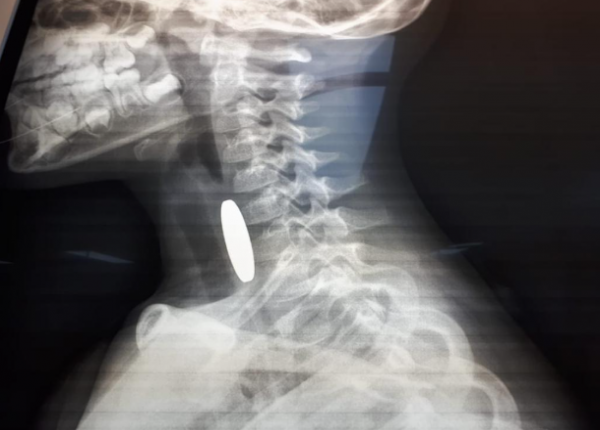

من جانبه قال الوكيل علاء السلايطة، أحد أفراد الدورية: “أثناء وجودنا في المنطقة استنجد بنا والد الطفل وهو يحمل ابنه، فقمنا مباشرة بتقديم الإسعافات الأولية المخصصة للأطفال دون سن الخامسة، وفقاً للتدريبات والدورات التي نتلقاها من مديرية الأمن العام للتعامل مع مثل هذه الحالات حتى بدأت حالته الصحية بالاستقرار واستكمال عملية إسعافه باتجاه المستشفى بواسطة المحطة الأمنية بعد أن تم التنسيق مع غرفة العمليات والسيطرة.